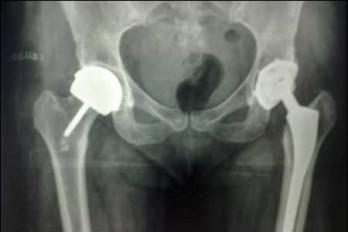

Un reemplazo articular no es más que la sustitución de una articulación dañada, el lugar donde dos o más huesos se unen (como la rodilla y cadera) por un material artificial llamado prótesis.

La prótesis de las caderas -segunda más frecuente- se reemplaza por dos causas: traumas o por artrosis. Para esto los pacientes tienen que ser sometidos a un tratamiento de esteroides por mucho tiempo. Existen otros factores de riesgos como lo es la edad (personas con 65 y 75 años también pasan por el proceso).

Los pacientes empiezan el proceso realizando una radiografía simple, puestos de pie.